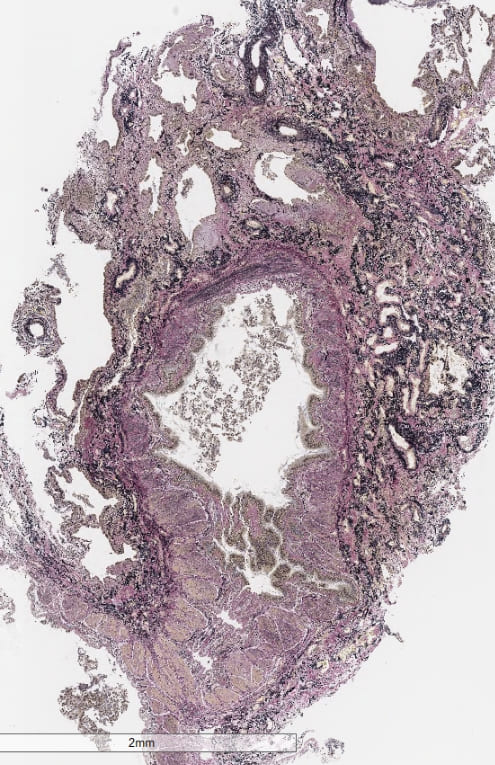

【クライオ肺生検組織】

右B8a:拡張気管支と、周囲の肺胞に細気管支上皮の被覆及び胞隔の線維性肥厚。

右B8b:拡張気管支と、周囲の肺胞の虚脱を伴う線維化。拡張した気腔にせり出す幼弱な線維芽細胞巣。

#fNSIP+UIPの混在